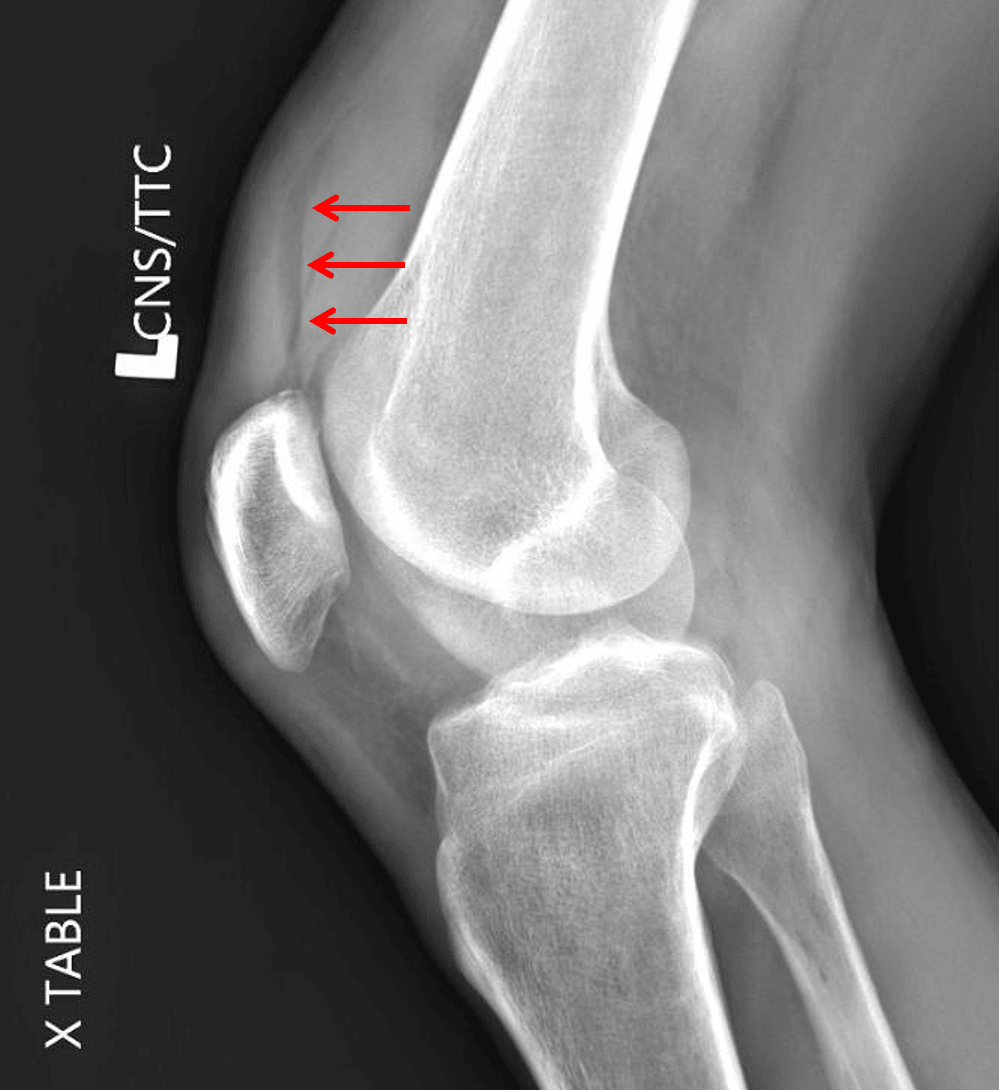

Findings

- Large lipohemarthrosis

- No acute fracture identified

Lipohemarthrosis

Large lipohemarthrosis without acute fracture identified. Consider CT for further evaluation.

- Cross-table lateral knee views are important in the setting of trauma to evaluate for lipohemarthrosis

- Lipohemarthrosis often results from an intra-articular fracture resulting in release of fat (“lipo”) and blood (“hemo”) into the joint space

- Look for a layering fat-fluid level on cross table lateral view

- When you see lipohemarthrosis and don’t see a fracture, always raise the possibility of an occult fracture and suggest CT or MRI for further evaluation

- This patient had an impaction fracture of the medial femoral condyle that was even subtle on CT

Lipohemarthrosis. Red arrows indicate the fat-fluid level.